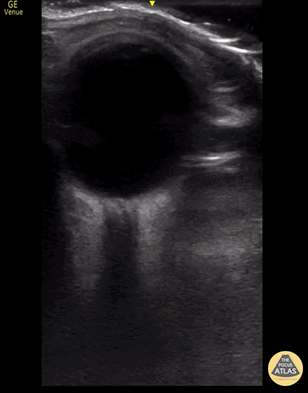

A hyperechoic focus noted in the distal optic nerve using a linear transducer concerning for an acute central retinal artery occlusion. Kody Sacks-Moynihan, MD; Steven Shapiro, DO; Jackie Nguyen, MD; Huy Tran, MD; Gaurav Patel, MD